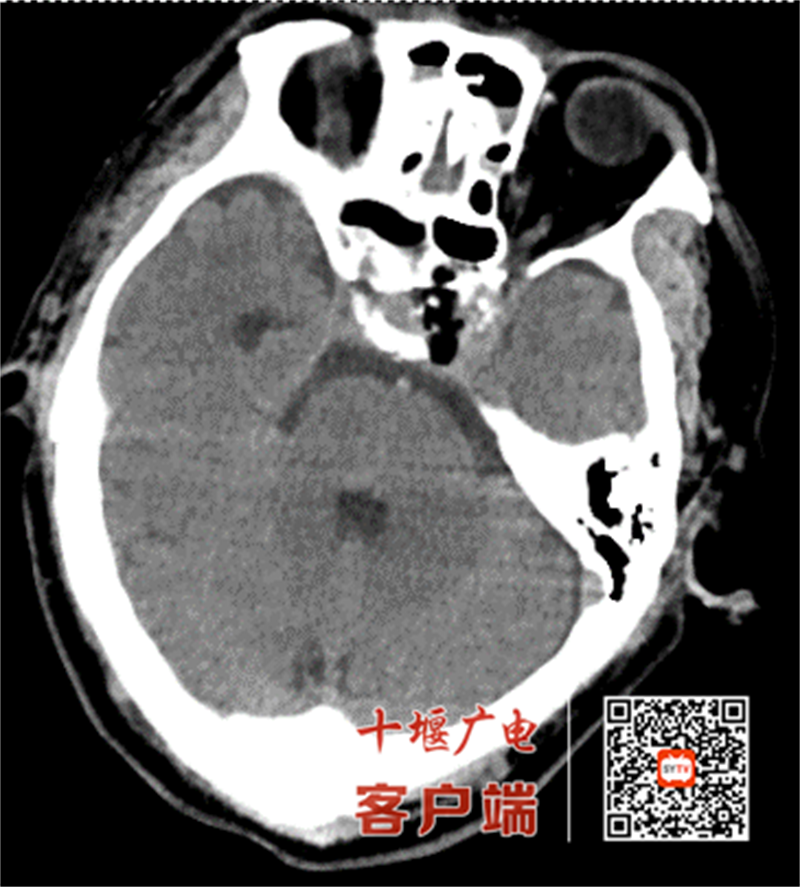

63歲的吳先生(化姓)門診體檢發(fā)現(xiàn)顱內(nèi)占位,入院后,顱腦磁共振檢查提示鞍區(qū)占位性病變,考慮垂體瘤可能性大。由于腫瘤毗鄰視神經(jīng)及頸內(nèi)動(dòng)脈等重要結(jié)構(gòu),且患者希望盡量微創(chuàng)行手術(shù)治療,十堰市人民醫(yī)院神經(jīng)外科團(tuán)隊(duì)經(jīng)多學(xué)科會(huì)診后,決定采用機(jī)器人導(dǎo)航聯(lián)合神經(jīng)內(nèi)鏡的經(jīng)鼻蝶入路方案。

手術(shù)當(dāng)日,團(tuán)隊(duì)先通過(guò)機(jī)器人系統(tǒng)融合患者頭顱CT與核磁影像,構(gòu)建3D腦部模型,精準(zhǔn)定位腫瘤位置,規(guī)劃最優(yōu)手術(shù)路徑,誤差控制在1毫米以內(nèi)。術(shù)中,在機(jī)器人實(shí)時(shí)導(dǎo)航與電生理監(jiān)測(cè)雙重保障下,醫(yī)生經(jīng)鼻腔自然腔道直達(dá)病灶,借助神經(jīng)內(nèi)鏡清晰視野分塊切除腫瘤,全程未損傷周圍正常腦組織及血管神經(jīng),術(shù)中出血量?jī)H50毫升。